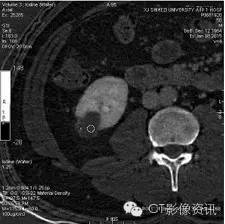

薄层图像三期观察,半数以上医生坚持有强化。初步诊断良性实质性占位。

进行能谱分析,碘含量测量,三期病变内部碘含量相似,且接近0的水平,提示病变没有强化。